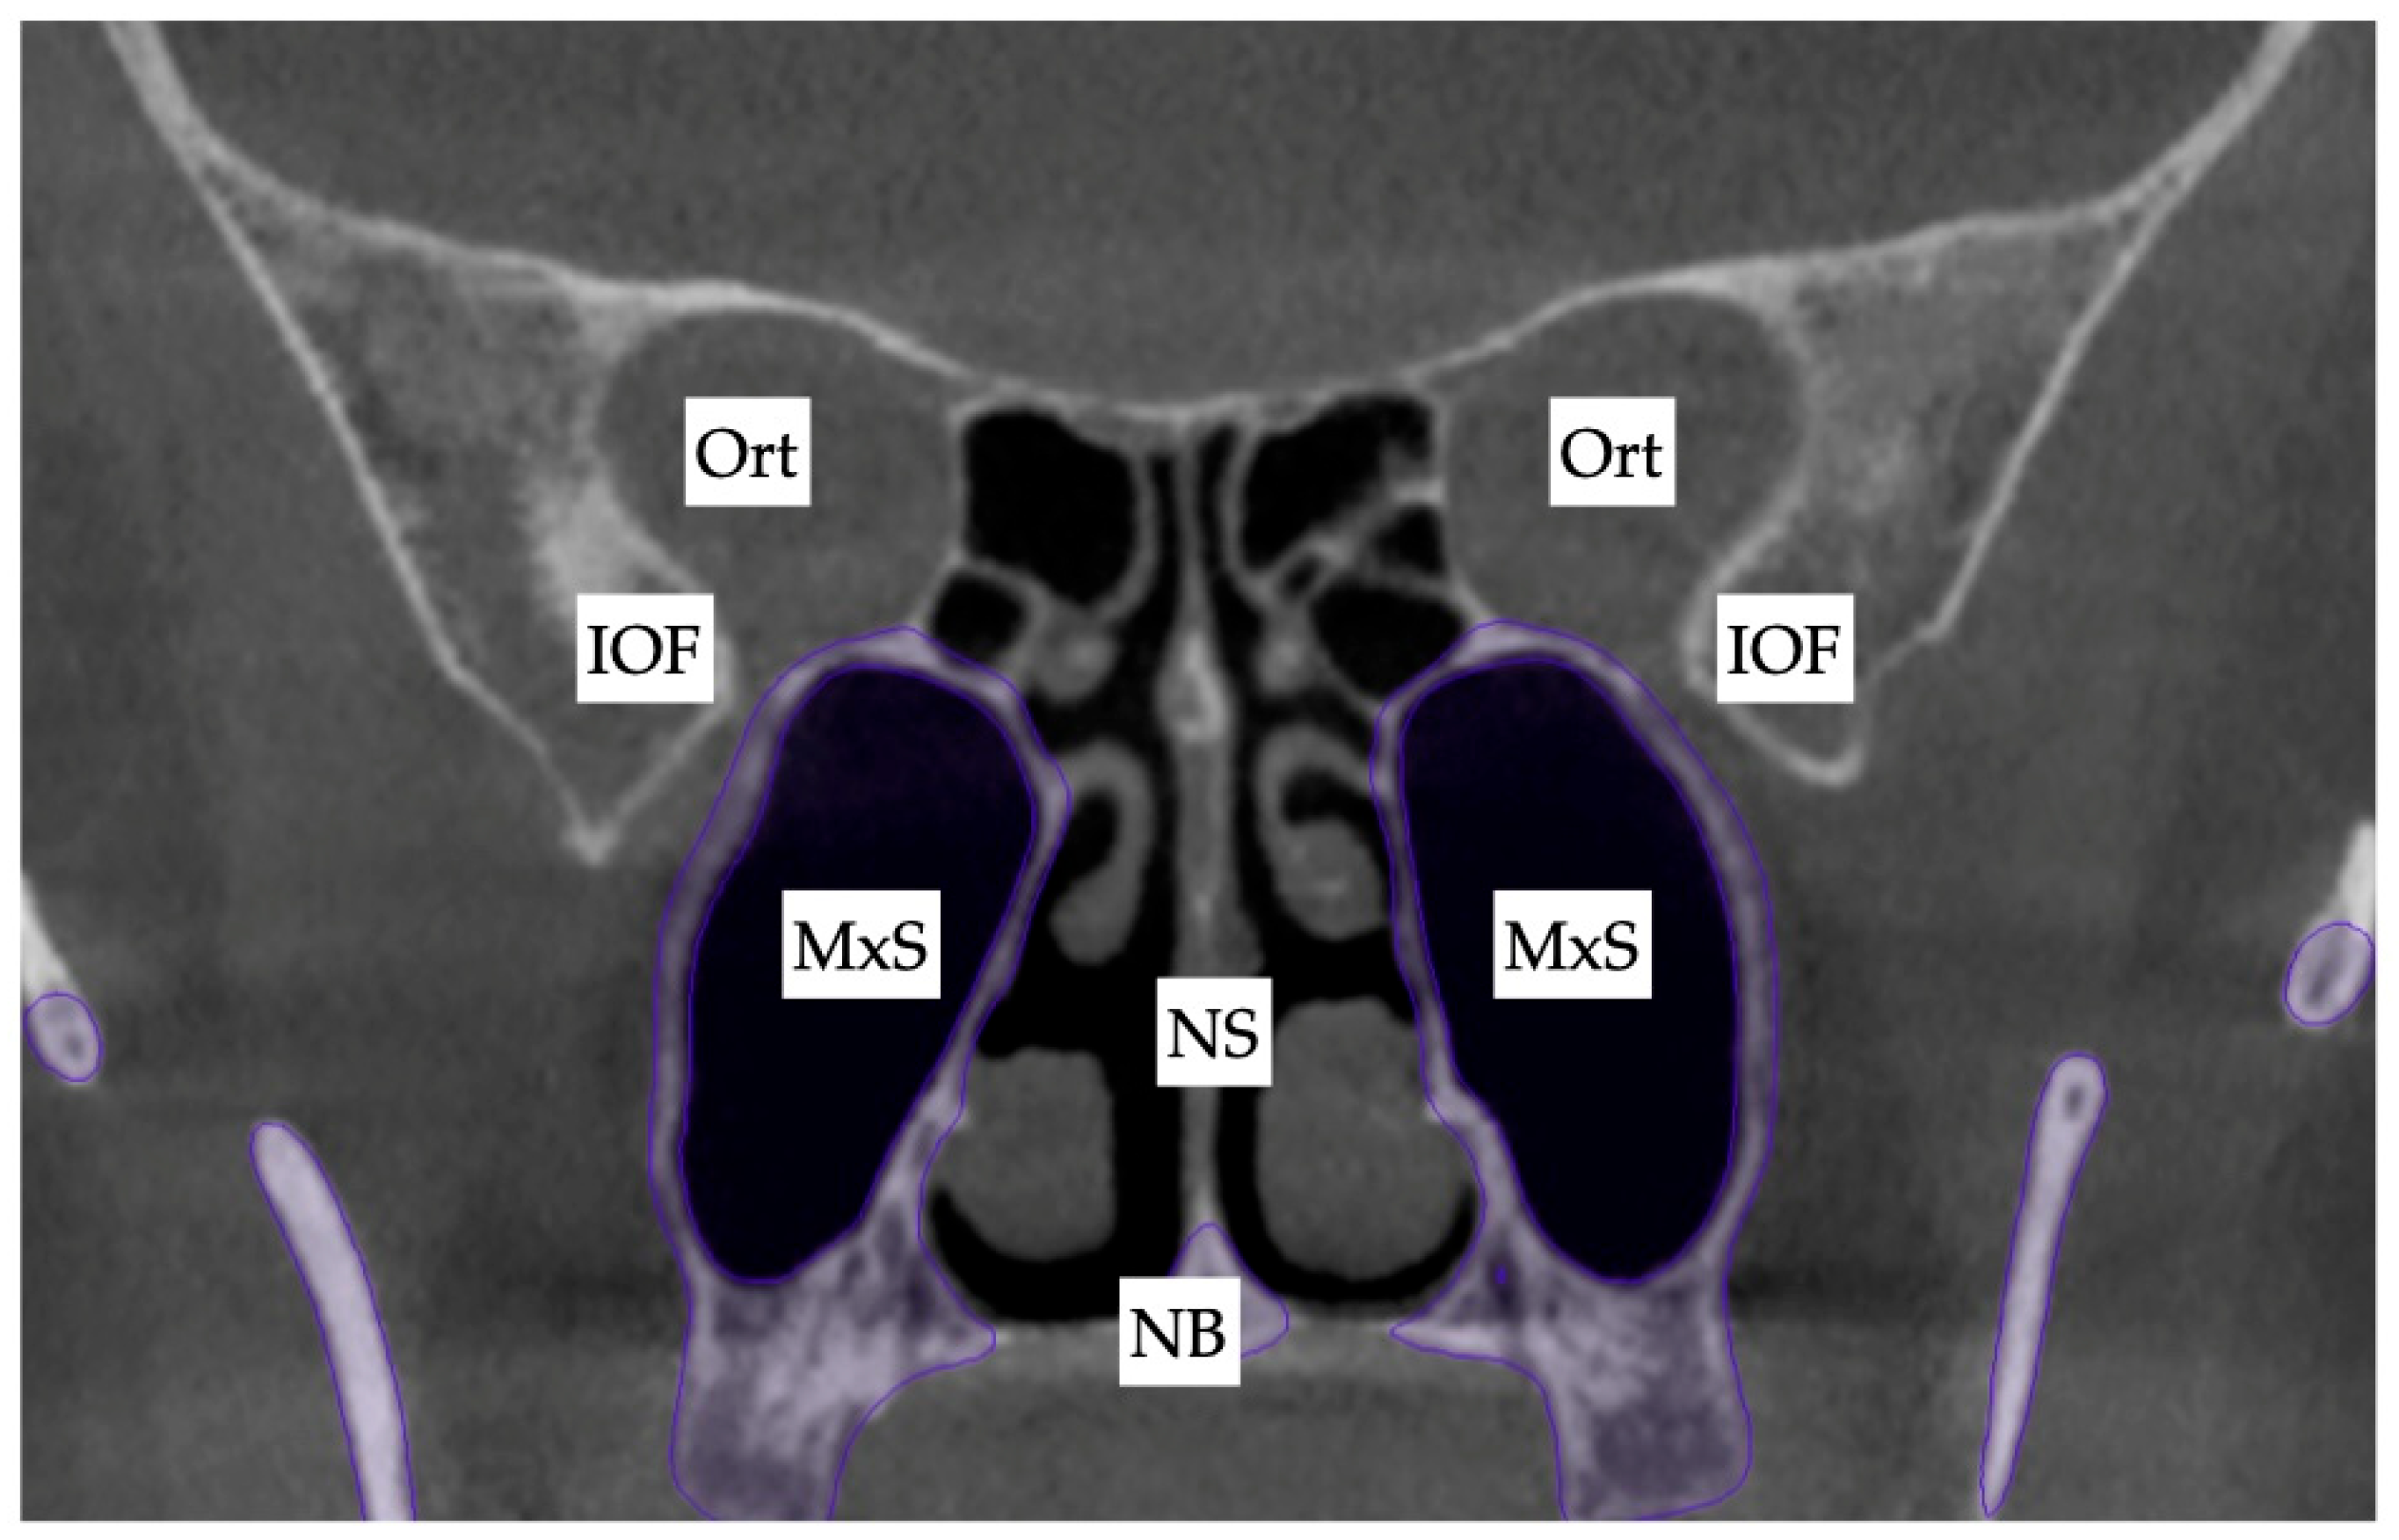

2. Materials and Methods

2.1. Pre-Treatment Records and Analysis

2.2. Pre-Treatment Diagnosis